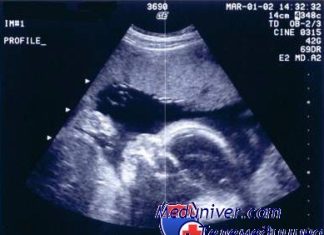

УЗИ при беременности. Влияние ультразвука на плод и частота, виды обследования

Беременность всегда сопряжена с переживаниями и волнением будущих родителей о судьбе своего ребёнка. Нормально...